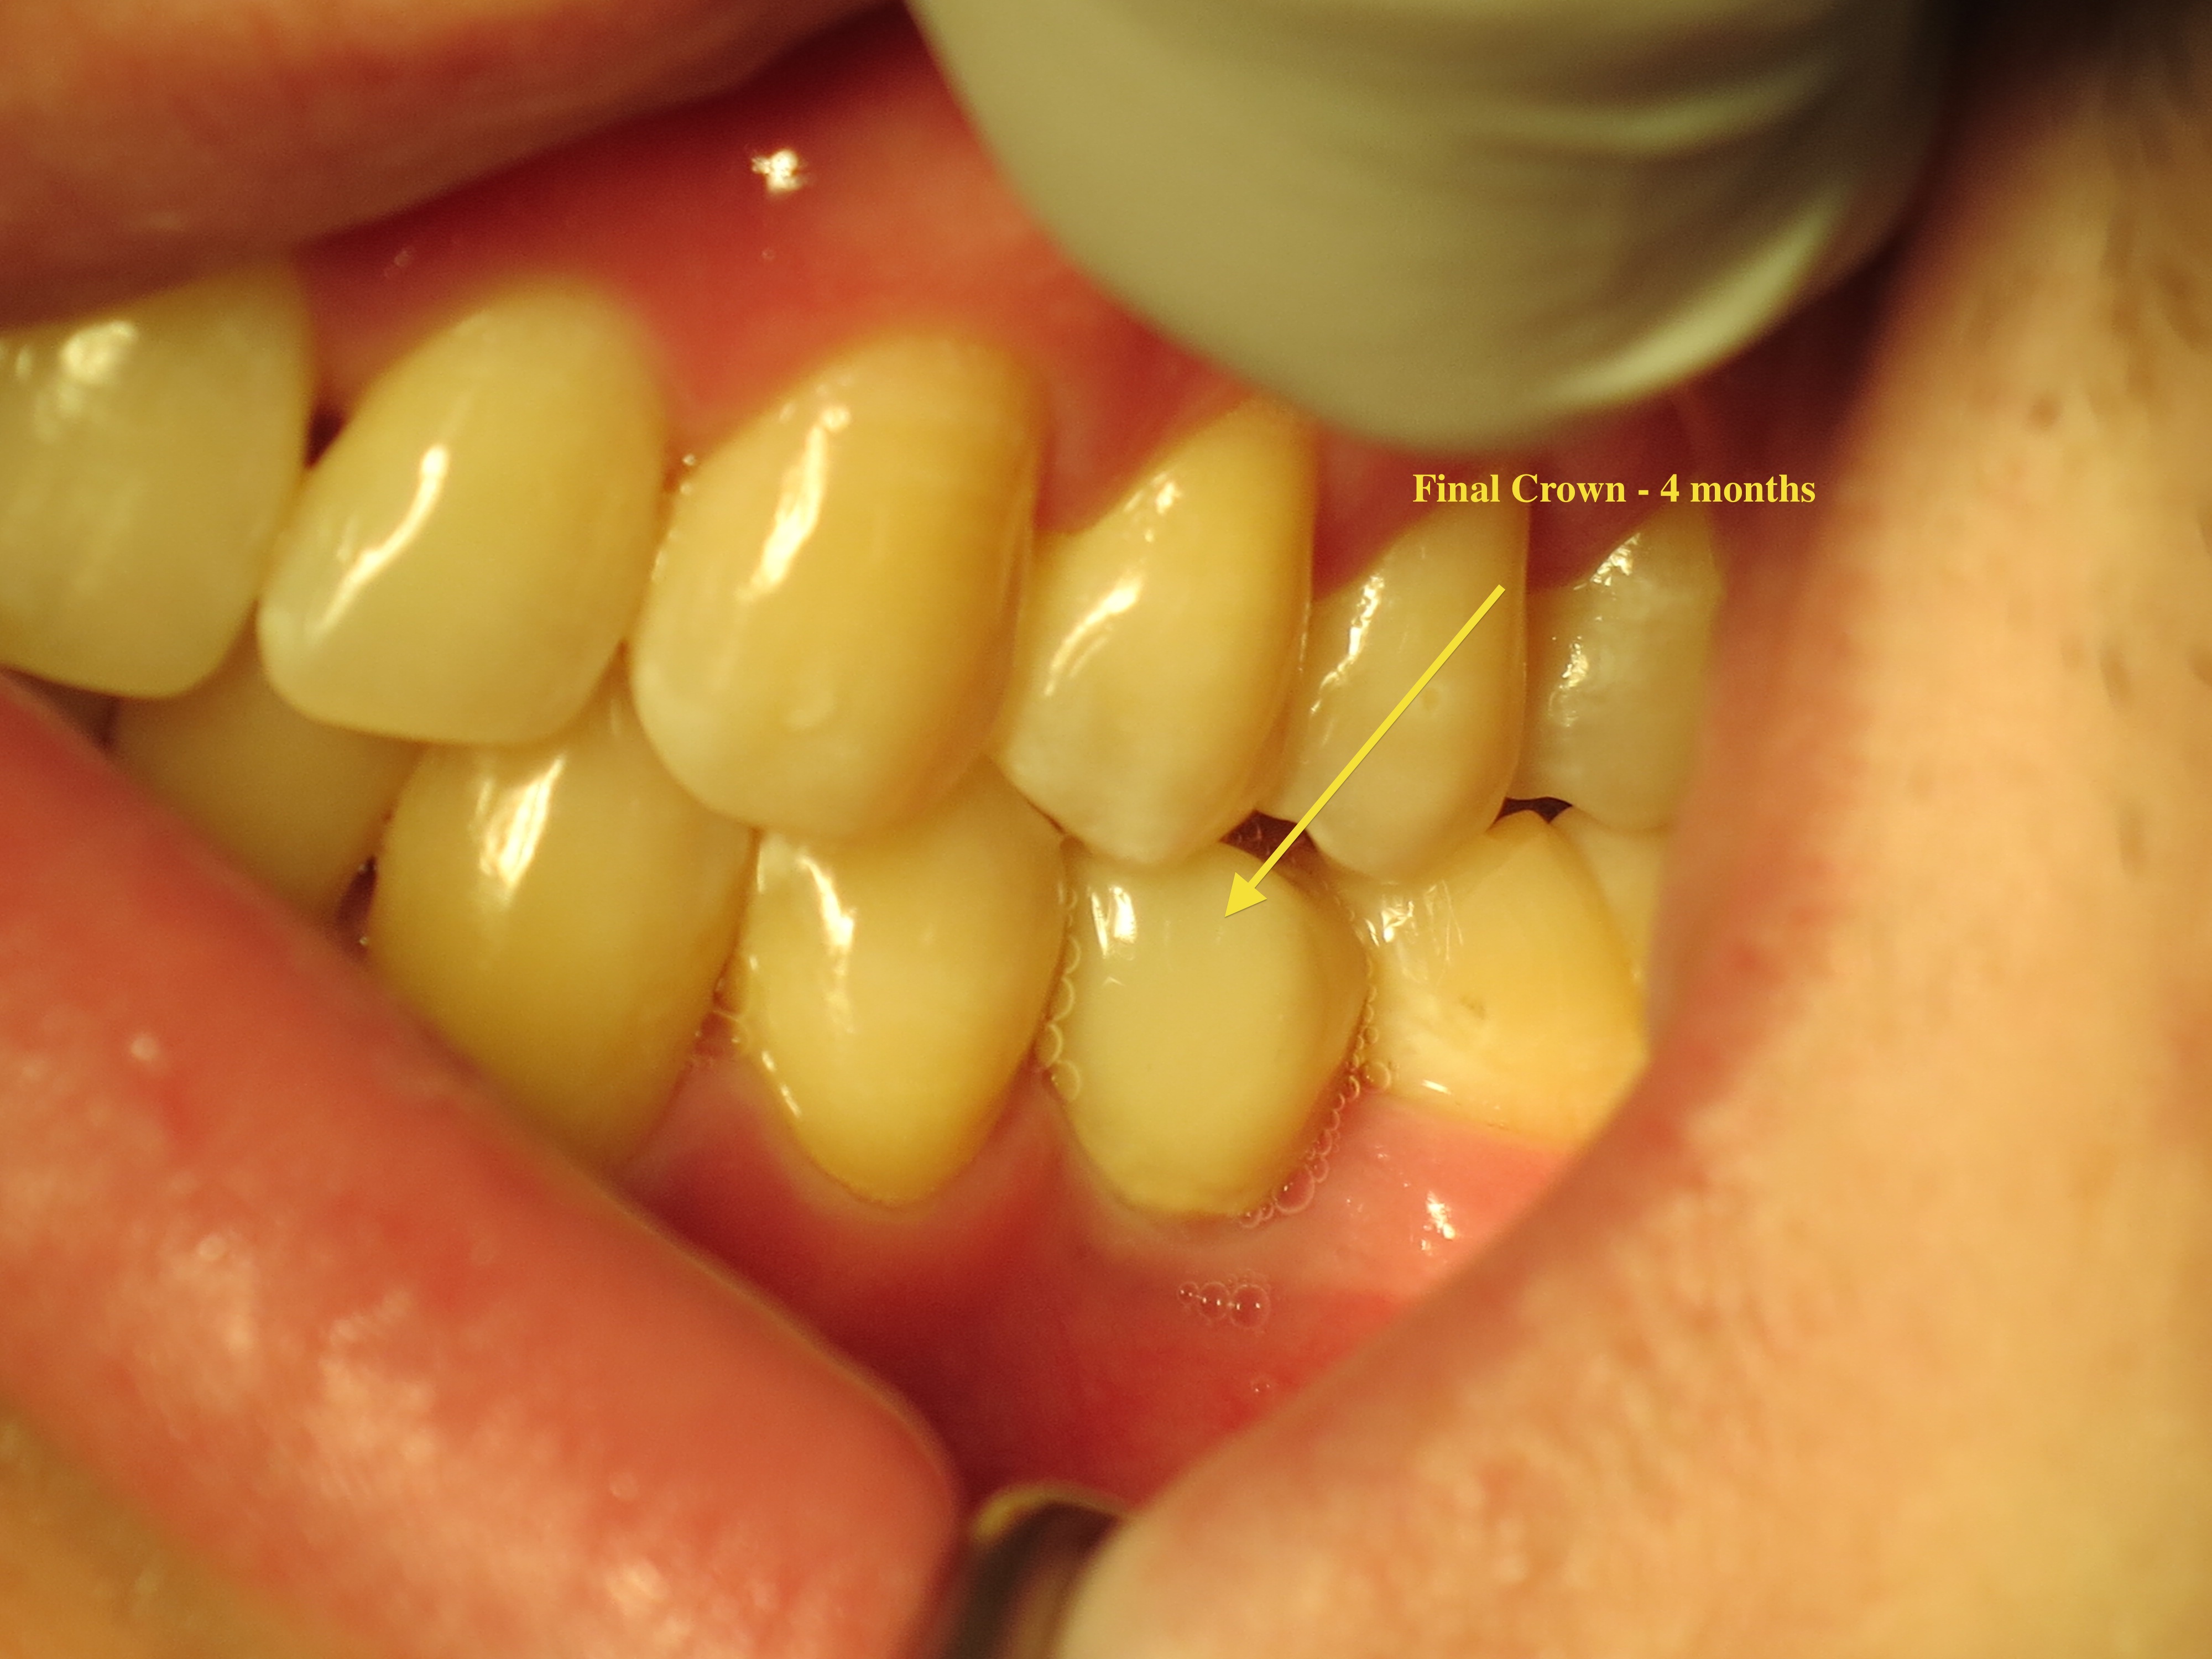

Replacement tooth = Implant Temporary crown on implant

Final Crown placed 4 months later